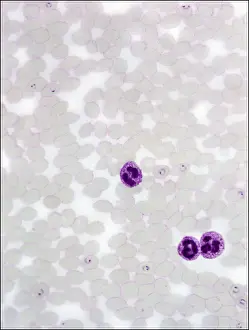

"Exploring the Intricate World of Protista: From Pressed Seaweed Specimens to Microscopic Wonders" In this captivating journey through the diverse realm of protista, we encounter a fascinating array of organisms. The pressed seaweed specimens C016 / 6127 reveal intricate patterns and textures that hint at the hidden beauty within. Diatoms, as seen under a scanning electron microscope (SEM), showcase their mesmerizing geometric shapes and delicate structures. Dictyota dichotoma, a brown algae commonly known as mermaid's fan, unveils its elegant fronds swaying in underwater currents. Illustrations depicting hummingbirds from the Trochilidae family remind us of the interconnectedness between these avian wonders and protists. These tiny creatures rely on nectar produced by flowering plants like Fucus bulbosus, a type of kelp found along coastal regions. Another diatom specimen captured under SEM reveals its intricate details, highlighting nature's artistry at microscopic scales. Fucus radiatus, another species of kelp with branching thalli resembling miniature forests beneath the waves, showcases its resilience in harsh marine environments. Moving beyond seaweeds and birds, illustrations introduce us to liverworts from the Hepaticae family - primitive land-dwelling plants that share an ancient lineage with protists. Their unique reproductive strategies have allowed them to thrive for millions of years. However, not all protists are benign or beneficial; some can cause harm. Plasmodium sp. , a malarial parasite transmitted by mosquitoes, serves as a stark reminder of how these microorganisms can impact human health. Radiolarians belonging to Acanthophracta group astonish with their intricate skeletal structures made up of silica shells. Coelosphaeridium presents yet another marvel – calcareous alga adorned with ornate patterns reminiscent of stained glass windows. Throughout this exploration into the world of protista, diatoms emerge as prominent protagonists.